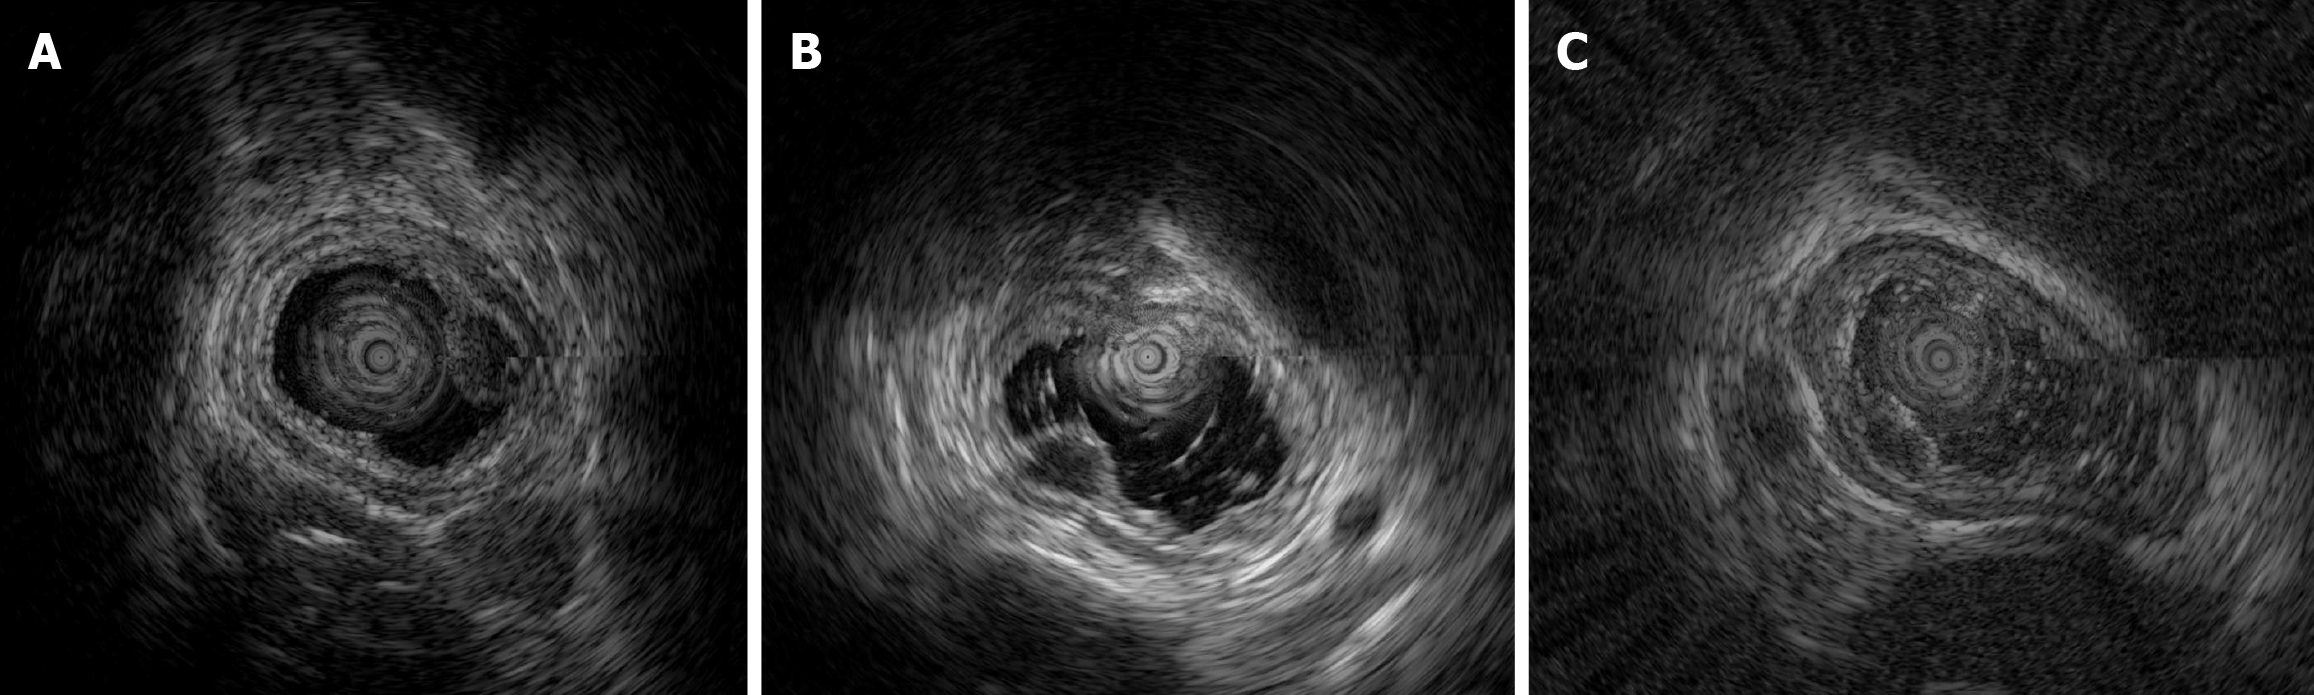

EUS was routinely performed according to well-acknowledged procedures using an Olympus EU-ME2 (Olympus Corporation, Tokyo, Japan) and mini probe with a frequency of 12 MHz. Among the patients with early E-NEC, three underwent EUS (Figure 3), which revealed solitary hypoechoic lesions originating from the muscularis mucosae or submucosa with homogeneous internal echogenicity, clear borders, normal peripheral esophageal hierarchical architecture, and intact muscularis mucosae and epithelial membranes. In one patient, multiple enlarged lymph nodes were observed outside the esophageal wall. The average grayscale value of EUS images for early E-NEC (n = 3) was significantly higher than that of esophageal leiomyoma [n = 8, 63.79 ± 1.42 vs 49.44 ± 11.57, P = 0.01, Cohen’s d = 1.402; 95% confidence intervals (CI): -0.2718 to 3.077], indicating that early E-NEC lesions exhibited higher echogenicity than esophageal leiomyomas (Figure 4).

Furthermore, E-NEC is associated with a high rate of lymph node metastasis, whereas esophageal leiomyomas are benign and rarely metastasize[11,25]. Thus, enlarged periesophageal lymph nodes on EUS should raise a suspicion of E-NEC. Although this study identified several distinguishing features between E-NEC and esophageal leiomyoma, including differences in EUS echogenicity and NBI images, as well as lymph node metastasis, there are some limitations that should be considered. First, as E-NECs are extremely rare, we included only four patients in our study, which limited the ability to derive more significant statistical interpretations. Although the observed effect size (Cohen’s d = 1.402) indicated a large difference between the two groups, the 95%CI of the effect size included 0, which may raise concerns regarding the robustness of the effect. This finding should also be interpreted in the context of a small sample size, which is known to inflate uncertainty in estimating effect sizes and widen CI, especially in studies with unequal group sizes. Importantly, despite the wide interval, the intergroup difference remained statistically significant (P = 0.01), suggesting that the observed effect was unlikely to be due to random chance. We believe that the inclusion of 0 in the CI reflects limited statistical power rather than the absence of a true effect. Thus, future clinical studies with larger sample sizes are needed to validate these observations and more precisely determine the true magnitude of the observed effect.